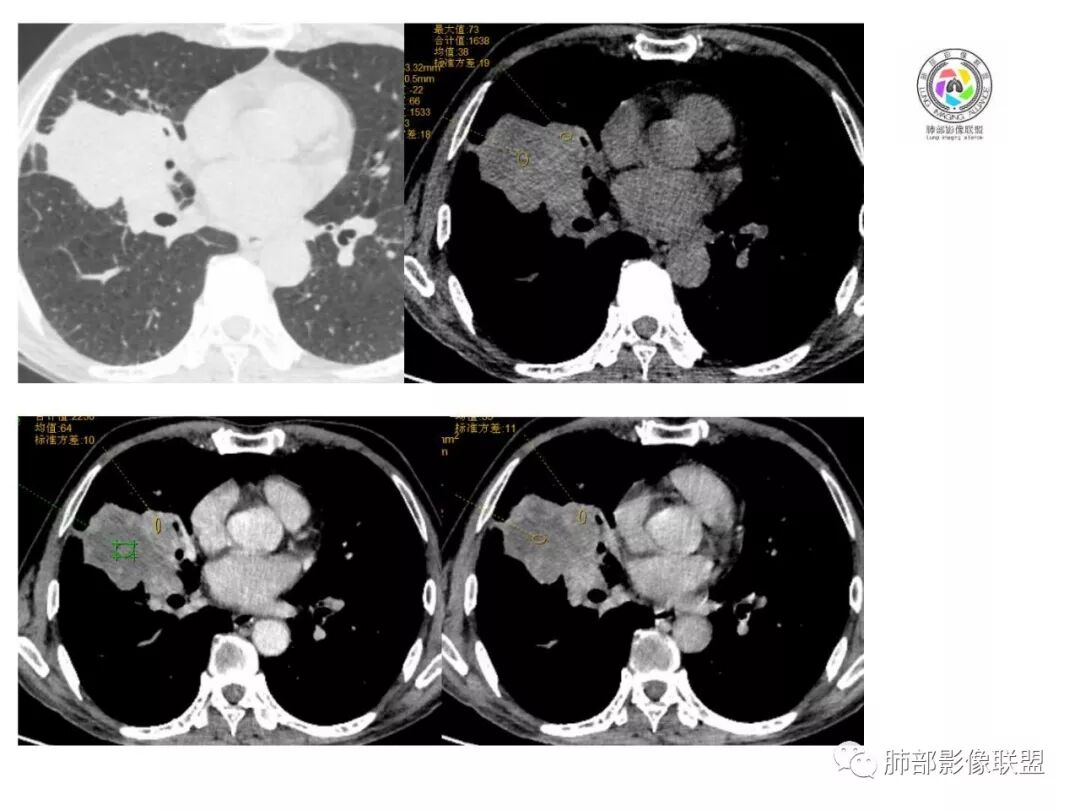

右肺巨大肿块,跨叶生长,其内见大片状坏死,坏死边界不清,血管进入,边缘受侵,病灶边缘可见毛刺及分叶,病灶强化方式速升速降,纵隔内见坏死强化淋巴结,周围肺叶小叶间隔结节样增厚,考虑恶性腺癌并淋巴结转移及癌性淋巴管炎,鉴别肉瘤。

右肺中叶可见类圆形软组织密度肿块影,右肺中叶外侧段支气管狭窄截断。肿块密度不均,边缘毛燥不规则,可见毛刺。远侧肺内可见网格条索影。增强后可见不均匀强化。纵隔淋巴结肿大,部分融合。考虑右肺恶性病变,鳞癌>腺癌,并纵隔淋巴结转移。

患者中老年男性,体检发现肺部占位。

胸CT:右肺中叶实性占位性病变,呈膨胀性生长,对斜裂明显挤压,右肺中叶外侧段阻塞,并在边缘可见分叶、毛刺、棘突样改变,胸膜牵拉;增强可见病灶明显强化,可见边缘模糊血管影,病灶内可见大片状低密度区,隆突下可见肿大淋巴结。

诊断考虑:恶性病变。

右肺巨大肿块,横跨上中下三叶,主体在中叶,外侧段近端支气管截断,膨隆分叶,毛刺,网格,淋巴结大,不均匀强化,湖泊样坏死,考虑恶性,低分化鳞癌>腺

右肺肿块,横跨上中下三叶,主体在中叶,外侧段近端支气管截断,膨隆分叶,毛刺,网格,淋巴结大,不均匀强化,有坏死,鳞癌?

老年男性,查体发现,右肺上叶中叶巨大肿块,有分叶,周围有条索影,支气管受压推移,内有大片及小灶坏死,坏死边界有的清楚有的不清,周围明显强化,纵隔有肿大淋巴结,跨叶生长,考虑恶性,腺癌或肉瘤样癌

右肺中叶可见类圆形软组织密度肿块影,支气管狭窄截断。肿块密度不均,边缘毛燥不规则,可见毛刺。增强后可见不均匀强化。纵隔淋巴结肿大,部分融合。考虑右肺恶性病变,鳞癌?

老年男性,右肺上叶可见一团块影,边界清,有膨隆,有凹陷,棘突,有分叶,密度不均匀,周边可见癌性淋巴管炎,跨叶裂,支气管阻塞?受压?狭窄,纵隔淋巴结肿大,考虑恶性,腺癌可能

右肺跨上叶与中叶一实性肿块影,中叶外侧段支气管堵塞,肿块有明显分叶、毛刺、棘突样改变,胸膜牵拉,周围有小花小草;增强可见病灶明显强化,病灶内可见大片状低密度区,以外侧为主,隆突下可见肿大淋巴结,恶性,考虑鳞癌可能。

老年人,右肺上叶软组织肿块,边界清晰,有浅分叶,右肺上叶支气管受阻,增强后病灶边缘强化,内部似有延迟强化,内见血管造影征,其血管边缘毛糙,纵隔可见增大淋巴结,考虑恶性肿瘤,无明显阻塞性肺炎和不张,考虑腺癌或腺鳞癌伴纵隔淋巴结转移

老年男性,体检发现右肺巨大肿块,右肺跨叶生长,可见支气管截断,边缘见分叶,毛刺,右肺支气管不通,增强后边缘强化,内部示大片低密度坏死区,边界不清,周围肺组织小叶间隔增厚,纵隔见多发肿大淋巴结。考虑为恶性并淋巴结转移。

右肺肺门肿块,自肺门向外延伸,外大内小,肿块呈长条状,平行支气管,近段支气管不规则堵塞,支气管无扩张壁无增厚,平扫密度均匀,增强后可见不规则坏死,病灶跨叶裂生长,纵隔淋巴结肿大,中老年男性,体检发现,无症状,考虑:恶性鳞癌,鉴别结核

老年男性,右肺跨裂生长团块灶,边缘浅分叶,内不均匀强化,无强化坏死区较多,可见支气管截断,周围阻塞性炎症,考虑恶性肿瘤可能,慢性肺脓肿待排

老年男性,右肺不规则跨叶肿块,有分叶,相邻支气管阻断,强化不均有低密度坏死区,坏死区边界较清,类似湖泊样,内见血管穿行,造影征,病灶远端可能有阻塞性炎症,总体考虑鳞癌。

患者中老年男性,体检发现右肺占位。血常规轻度贫血,AFP、CEA正常,肝肾功能、血糖、血脂、心肌酶、电解质正常。胸部CT:右肺中叶巨大肿块灶,垮叶生长,可见分叶、毛刺、血管集束、支气管截断征象,远端周围可见小叶间隔增厚,增强轻度强化,内可见低密度坏死区,综合淋巴结肿大,且可见淋巴结内似低密度灶。综合考虑恶性,鳞癌并癌性淋巴管炎可能大。鉴别结核、腺癌。

胸CT:右肺中叶团块样实性占位,边缘膨隆,中叶外侧段阻塞,病灶可见深分叶、棘突,胸膜牵拉;增强不均匀强化,可见边缘模糊血管影,病灶内大片状低密度区,纵隔多发肿大淋巴结。

诊断考虑:恶性病变,鳞?大细胞?鉴别:TB

右肺中叶巨大肿块,外侧段近端支气管截断,横跨上中下三叶,主体在中叶,膨隆分叶,毛刺,网格,淋巴结大,不均匀强化,伴阻塞性肺炎及肺不张,湖泊样坏死,考虑恶性,鳞癌可能性较大

右肺上叶肿块,跨叶生长,分叶,支气管截断,周围支气管受压推移,内有大片坏死,周围小叶间隔增厚,纵隔淋巴结肿大,明显强化,考虑肉瘤样癌。鉴别腺鳞癌。

病灶主体位于右肺中叶,跨上、下叶,分叶毛刺,外侧段支气管堵塞,大片坏死,边界不清,内见血管进入,增强快进快出,纵隔淋巴结肿大,小叶间隔增厚,恶性,腺癌或肉瘤样癌可能。

右肺门旁肿块,形态不规则,跨叶生长,近段支气管不规则堵塞,支气管局部增厚,密度欠均匀,增强后可见不规则坏死,纵隔淋巴结肿大,中老年男性,体检发现,考虑:恶性鳞癌